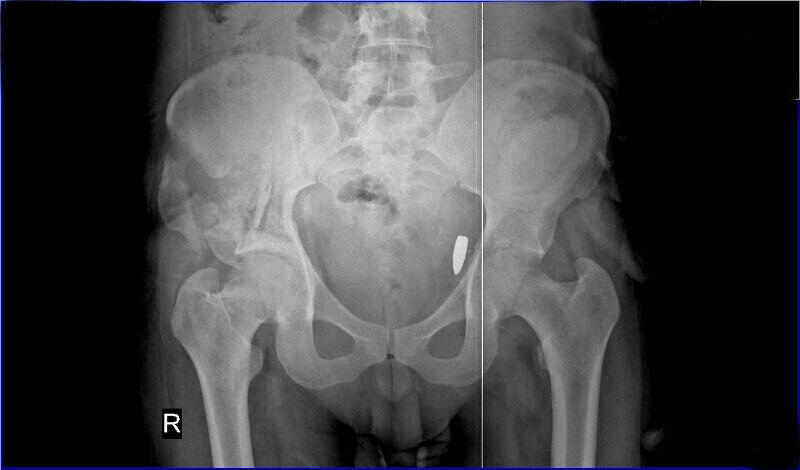

When we talk to him he is eager to show us the X-ray. There, clearly, is the image of a bullet lodged next to his pelvis bone. The bullet is a threat to his life, but that didn't stop him from embarking on an extraordinary, and extraordinarily dangerous, trek. It almost ended as it was beginning, in a small dinghy in the narrow strait between Bodrum, Turkey, and the Greek island of Kos, where thousands of refugees have arrived in recent weeks.

"When I woke up, my brother Ahmed came. He explained to me that they removed part of my colon. Then the doctor came and showed me the bullets they took out. He showed me four bullets. One was still inside my body."

The doctor also told Ali he couldn't remove the last bullet; it was dangerously lodged in his groin, and he didn't have the expertise to take it out. Ali's best chance of complete recovery lay with a specialized hospital in Berlin. He would also need surgery to repair his shattered hip. His intestines are held in place by an internal abdominal binder.